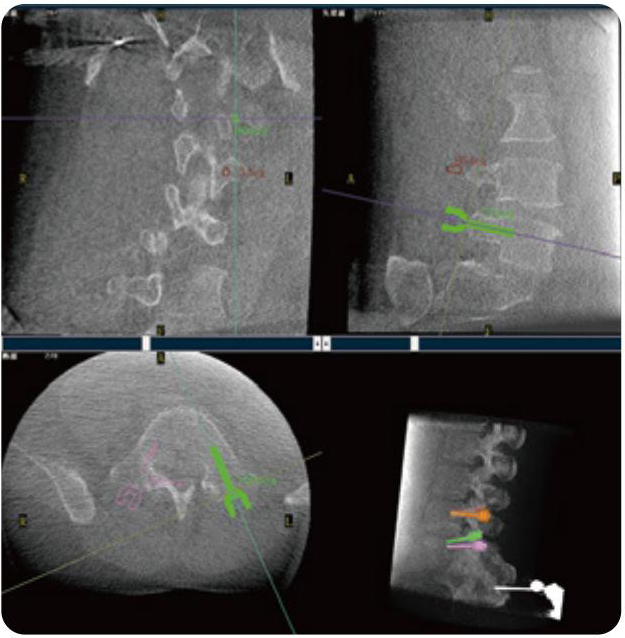

PL300B可應用于多節(jié)段脊柱外科手術,輔助醫(yī)生定位病灶部位,為脊柱外科手術(經(jīng)皮椎體成形術、椎弓根螺釘內(nèi)固定術等術式)提供術前手術流程規(guī)劃、入釘位置、角度可視化引導,模擬仿真入釘輔助。

PL300B搭配普愛醫(yī)療自主研發(fā)生產(chǎn)的平板3D C形臂,借助一體化自適應配準( 軌跡配準)技術,通過追蹤C形臂三維采集軌跡,自動完成圖像坐標建立和系統(tǒng)坐標配準。配準精度更高,操作步驟少,系統(tǒng)運作效率高。